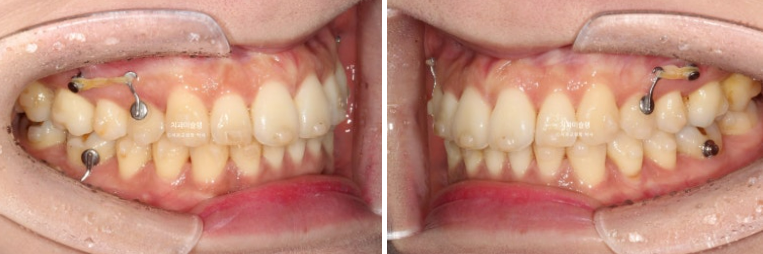

2년 전 교정치료를 위해 온 30대 환자분입니다. 파란 화살표 볼쪽으로 튀어나간 어금니들이 보입니다.

중심선 불일치도 보입니다.

앞니뻗침으로 인한 돌출이 있고

좌측에는 가위교합이 소구치에 하나 대구치에 하나 총 2군데 있습니다.

교합을 담당하는 어금니 중 절반이 가위교합 상태이니, 좌측으로 씹기가 힘든 상태입니다.